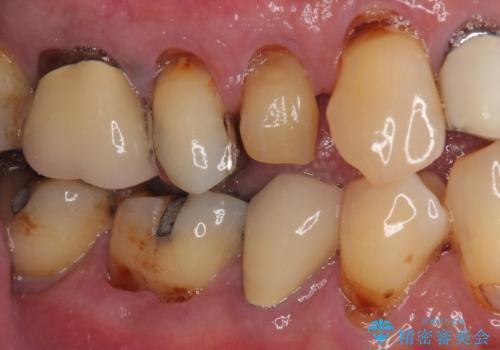

- 抜歯が必要なのでは?と近医で言われ、歯の保存を希望して来院された患者様です。

既に別の部位にインプラント治療を受けており、そのときの治療期間と苦労を鑑みて、何とか歯を残したいとのことで来院されました。

該当歯の状態としては何とか保存可能でしたが、予後不良のため、将来的にインプラント治療が必要となる可能性の高い状態でした。

当院での根管治療および歯周外科治療を併用した保存療法、並びに1DAYインプラントによる短期間インプラント治療の双方をご説明し、即日でインプラント治療を選択されました。

仮歯を用意した上で、抜歯即時埋入・即時荷重インプラントによる補綴治療を行うこととしました。